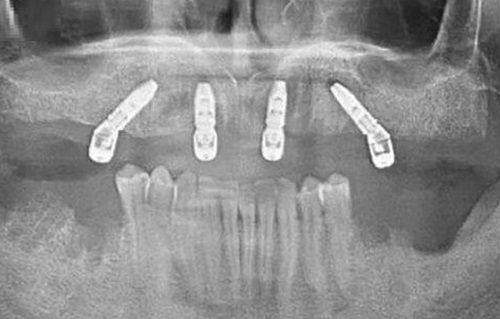

特别多人在选择口腔诊所时,更担心的就是医生的专精水平。毕竟,牙齿问题可不能马虎,一个不专精的医生可能会让问题变得更糟。上海朱荷兰口腔诊所拥有一支经验多、技术不错的专精团队。诊所的医生们都经过严格的专精培训,具备扎实的理论知识和丰富的临床经验。无论是常见的牙齿美白、补牙,还是复杂的种植牙、正畸手术,他们都能游刃有余地应对。他们会根据每位患者的具体情况,制定个性化的治疗方案,确保治疗成效达到至佳。